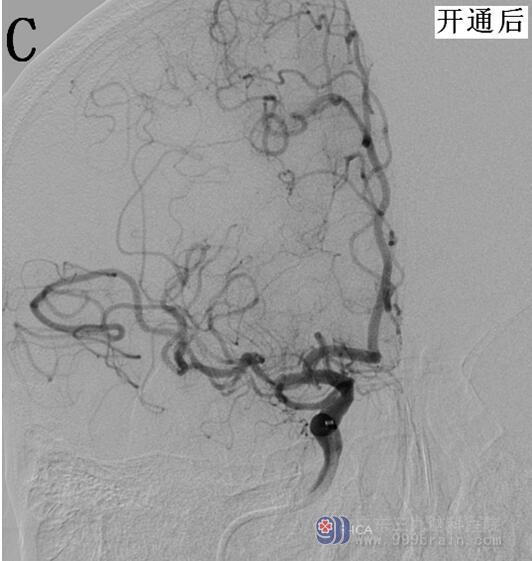

我院为患者立即开通卒中绿色通道,急查头颅DWI:右侧基底节、半卵圆中心、颞叶内侧、顶枕叶皮层多发急性梗塞灶,头部CTA显示右侧大脑中动脉M1段闭塞(图1);头部CT未见急性出血灶。诊断:“1.急性脑梗死;2.右侧大脑中动脉闭塞;3.高血压病2级 极高危组”明确。

图1 A:头颅CTA显示右侧大脑中动脉M1段闭塞(2017/9/6 18:38)

结合患者病史及查体评估,具有静脉溶栓指征,无禁忌症。请示王展航科主任后建议rt-PA静脉溶栓治疗,溶栓后桥接脑血管造影评估血管情况。告知患者家属病情,家属知情并同意溶栓及介入治疗。19:48开始使用rt-PA(50mg),15分钟后患者症状改善,左下肢肌力3+级,双侧眼球左侧活动稍受限,双眼右向凝视,构音欠清,左侧肢体肌力0级,右侧肢体肌力5级,伸舌左偏,左下肢病理征(+),NIHSS评分10分。20:15推入DSA室,行脑血管造影显示右侧大脑中动脉仍存在闭塞,立即桥接取栓+支架置入治疗,约22:30手术结束,术后大脑中动脉上干开通,血流速度恢复,大脑中动脉下干远端闭塞,但大脑前动脉可部分代偿,患者安返病房,生命体征平稳,复测患者NIHSS为6分,溶栓及桥接治疗有效(图2)。复查头部CT,明确无再通后出血,维持血压,预防患者再灌注损伤,定期评估患者NIHSS评分,密切关注生命体征,24小时后启动抗血小板治疗。8天后患者病情明显好转,肢体已恢复部分活动,可自行行走,查体仅遗留左侧肢体肌力5-级,余神经科查体无明显阳性体征。NIHSS:2分。请示王展航科主任,可予带药出院,嘱低盐低脂饮食,戒烟戒酒,控制血压。

图2 A、B为开通前的脑血管造影;C、D为脑血管开通后的造影显像